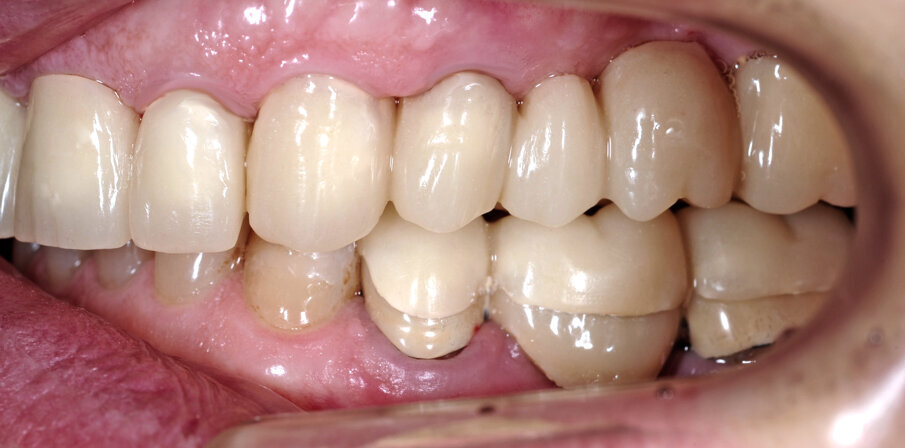

Il fresato ottenuto è poi riportato su articolatore Reference SL – già opportunamente programmato – e viene dall’Odontotecnico competente più precisamente funzionalizzato secondo i criteri della programmazione funzionale sequenziale, evidenziando con cere colorate i rapporti di centrica, le funzioni di mediotrusiva e protrusiva e le protezioni retrusive. I monconi sfilabili consentono la modellazione della sequenzialità mediotrusiva con la guida incisale indicata dalla registrazione axiografica (blu) (Figg. 34-37). La ceratura sequenziale è ora scansita con Sirona InEos X5 su Exocad, ed il modellato viene ricontrollato al CAD per spessori, connessioni e morfologia, e nella regolazione degli offsets per la ripreparazione dei monconi, ed è inviato al CAM per la fresatura dei II provvisori in Bredent breCAM.multicom, un PMMA con microriempitivo ceramico ad alta stabilità, su Dental Plus 5 Axis Milling Machine. La rifinitura dei monconi è seguita da ribasatura dei II provvisori in TRP - previo isolamento di tutte le superfici funzionali - e gli stessi sono poi rifiniti e lucidati. I soli elementi 3.3, 4.2 e 4.3 sono rimodellati in regione incisale con addictions in composito, secondo la morfologia studiata in ceratura. La consegna conferma la buona integrazione dei manufatti dal punto di vista estetico, occlusale, articolare e neuromuscolare, con controllo occlusale conforme al progetto (Figg. 38-42).

Il paziente utilizza questi secondi provvisori per otto settimane, durante le quali conferma la buona integrazione dei restauri e la soddisfacente funzione occlusale. Ciò è verificato con l’esecuzione di una nuova axiografia elettronica che già a due settimane dalla consegna evidenzia una buona risposta muscolare al nuovo design occlusale ed alla nuova postura mandibolare in TRP (Figg. 43-46). Provvediamo infine alle impronte per la costruzione dei manufatti definitivi in Zirconia-ceramica. I modelli sono scansiti in laboratorio con inEos X5 (Dentsply Sirona) su exocad (Figg. 47-49), ed una seconda scansione viene eseguita con i provvisori del Paziente posizionati sui modelli (Figg. 50-52). Il CAD consente di eseguire un matching fra le due scansioni, per cui i secondi provvisori utilizzati in TRP, con funzione occlusale sequenziale già completamente programmata, sono utilizzati per definire le morfologie dentali definitive di tutti gli elementi da restaurare (Figg. 53, 54) secondo il rapporto intermascellare definito (Figg. 55-58). Si esegue quindi fresatura al CAM della protesi definitiva in zirconia (Figg. 59, 60), la stratificazione e finitura ed infine la consegna al Paziente con cementazione in Panavia V5 (Figg. 61-65).